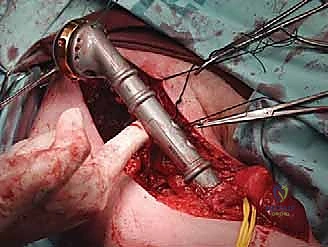

العزل العصبي الوعائي: هذه هي الخطوة الأهم. باستخدام أدوات الجراحة الميكروسكوبية ونظارات التكبير (Loupes)، يتم تحديد وعزل الأعصاب والأوعية الدموية وحمايتها بأشرطة ملونة.

استئصال الورم: يتم قص العظم بمنشار جراحي دقيق أعلى وأسفل الورم بمسافة أمان (Margin)، ويتم استخراج الكتلة الورمية بالكامل وإرسالها لمختبر الباثولوجي.

إعادة البناء الميكانيكي: يتم إدخال المكونات المعدنية (سواء مسمار نخاعي، شرائح، أو مفصل صناعي) وتثبيتها بقوة باستخدام الإسمنت العظمي إذا لزم الأمر. يتم التأكد من ثبات الهيكل الجديد تحت جهاز الأشعة السينية المباشر (C-arm).